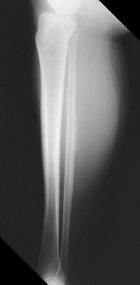

D.V. - 66 year old white female with a three month history of left calf mass

Zoom image: Radiological image Radiological image.